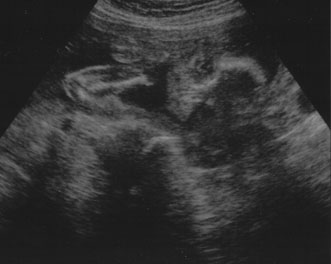

A second trimester ultrasound is usually done at 20 to 22 weeks' gestational age. The most commonly used fetal measurements are biparietal diameter, length of the femur or other long bones, and abdominal and head circumference. In addition to measurements, an anatomic survey is also done to evaluate the fetal brain (Fig. 9), spine, stomach, heart, kidneys, placental location and assessment of amniotic fluid (Fig. 10). If maternal risk factors are present, tetra screening results are abnormal, or there are abnormal findings on the anatomic survey, the patient is sent for a comprehensive ultrasound. The components of a comprehensive ultrasound are shown in Table 9. The ultrasound findings associated with Down syndrome include cardiac defects or enlargement, cystic hygroma (Fig. 11), duodenal atresia (Fig. 12), omphalocele, polyhydramnios, choroids plexus cyst, and renal calyceal dilation.

Fig. 9. Transaxial ultrasound of fetal heads.